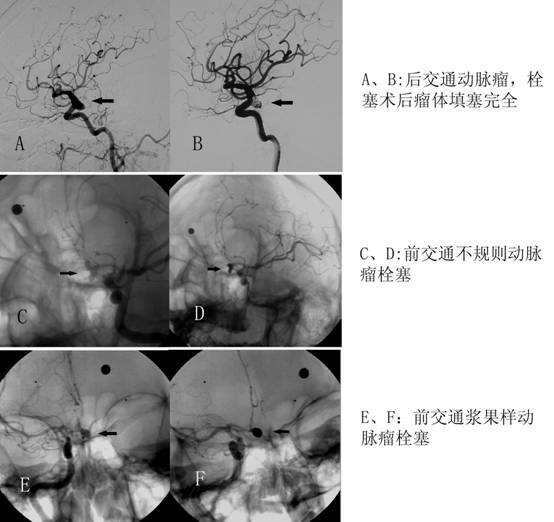

神经介入在临床上包括诊断和治疗两大类,神经介入治疗通过血管成形、栓塞等技术对病变血管进行局部治疗,具有创伤小、痛苦少及恢复快、效果明显的特点。

我科是广西率先开展脑血管病介入治疗的医院之一,多年来我科在该技术的临床应用方面取得了丰富的经验。无论是在高危患者及复杂手术的治疗上均获得了较好的临床疗效。